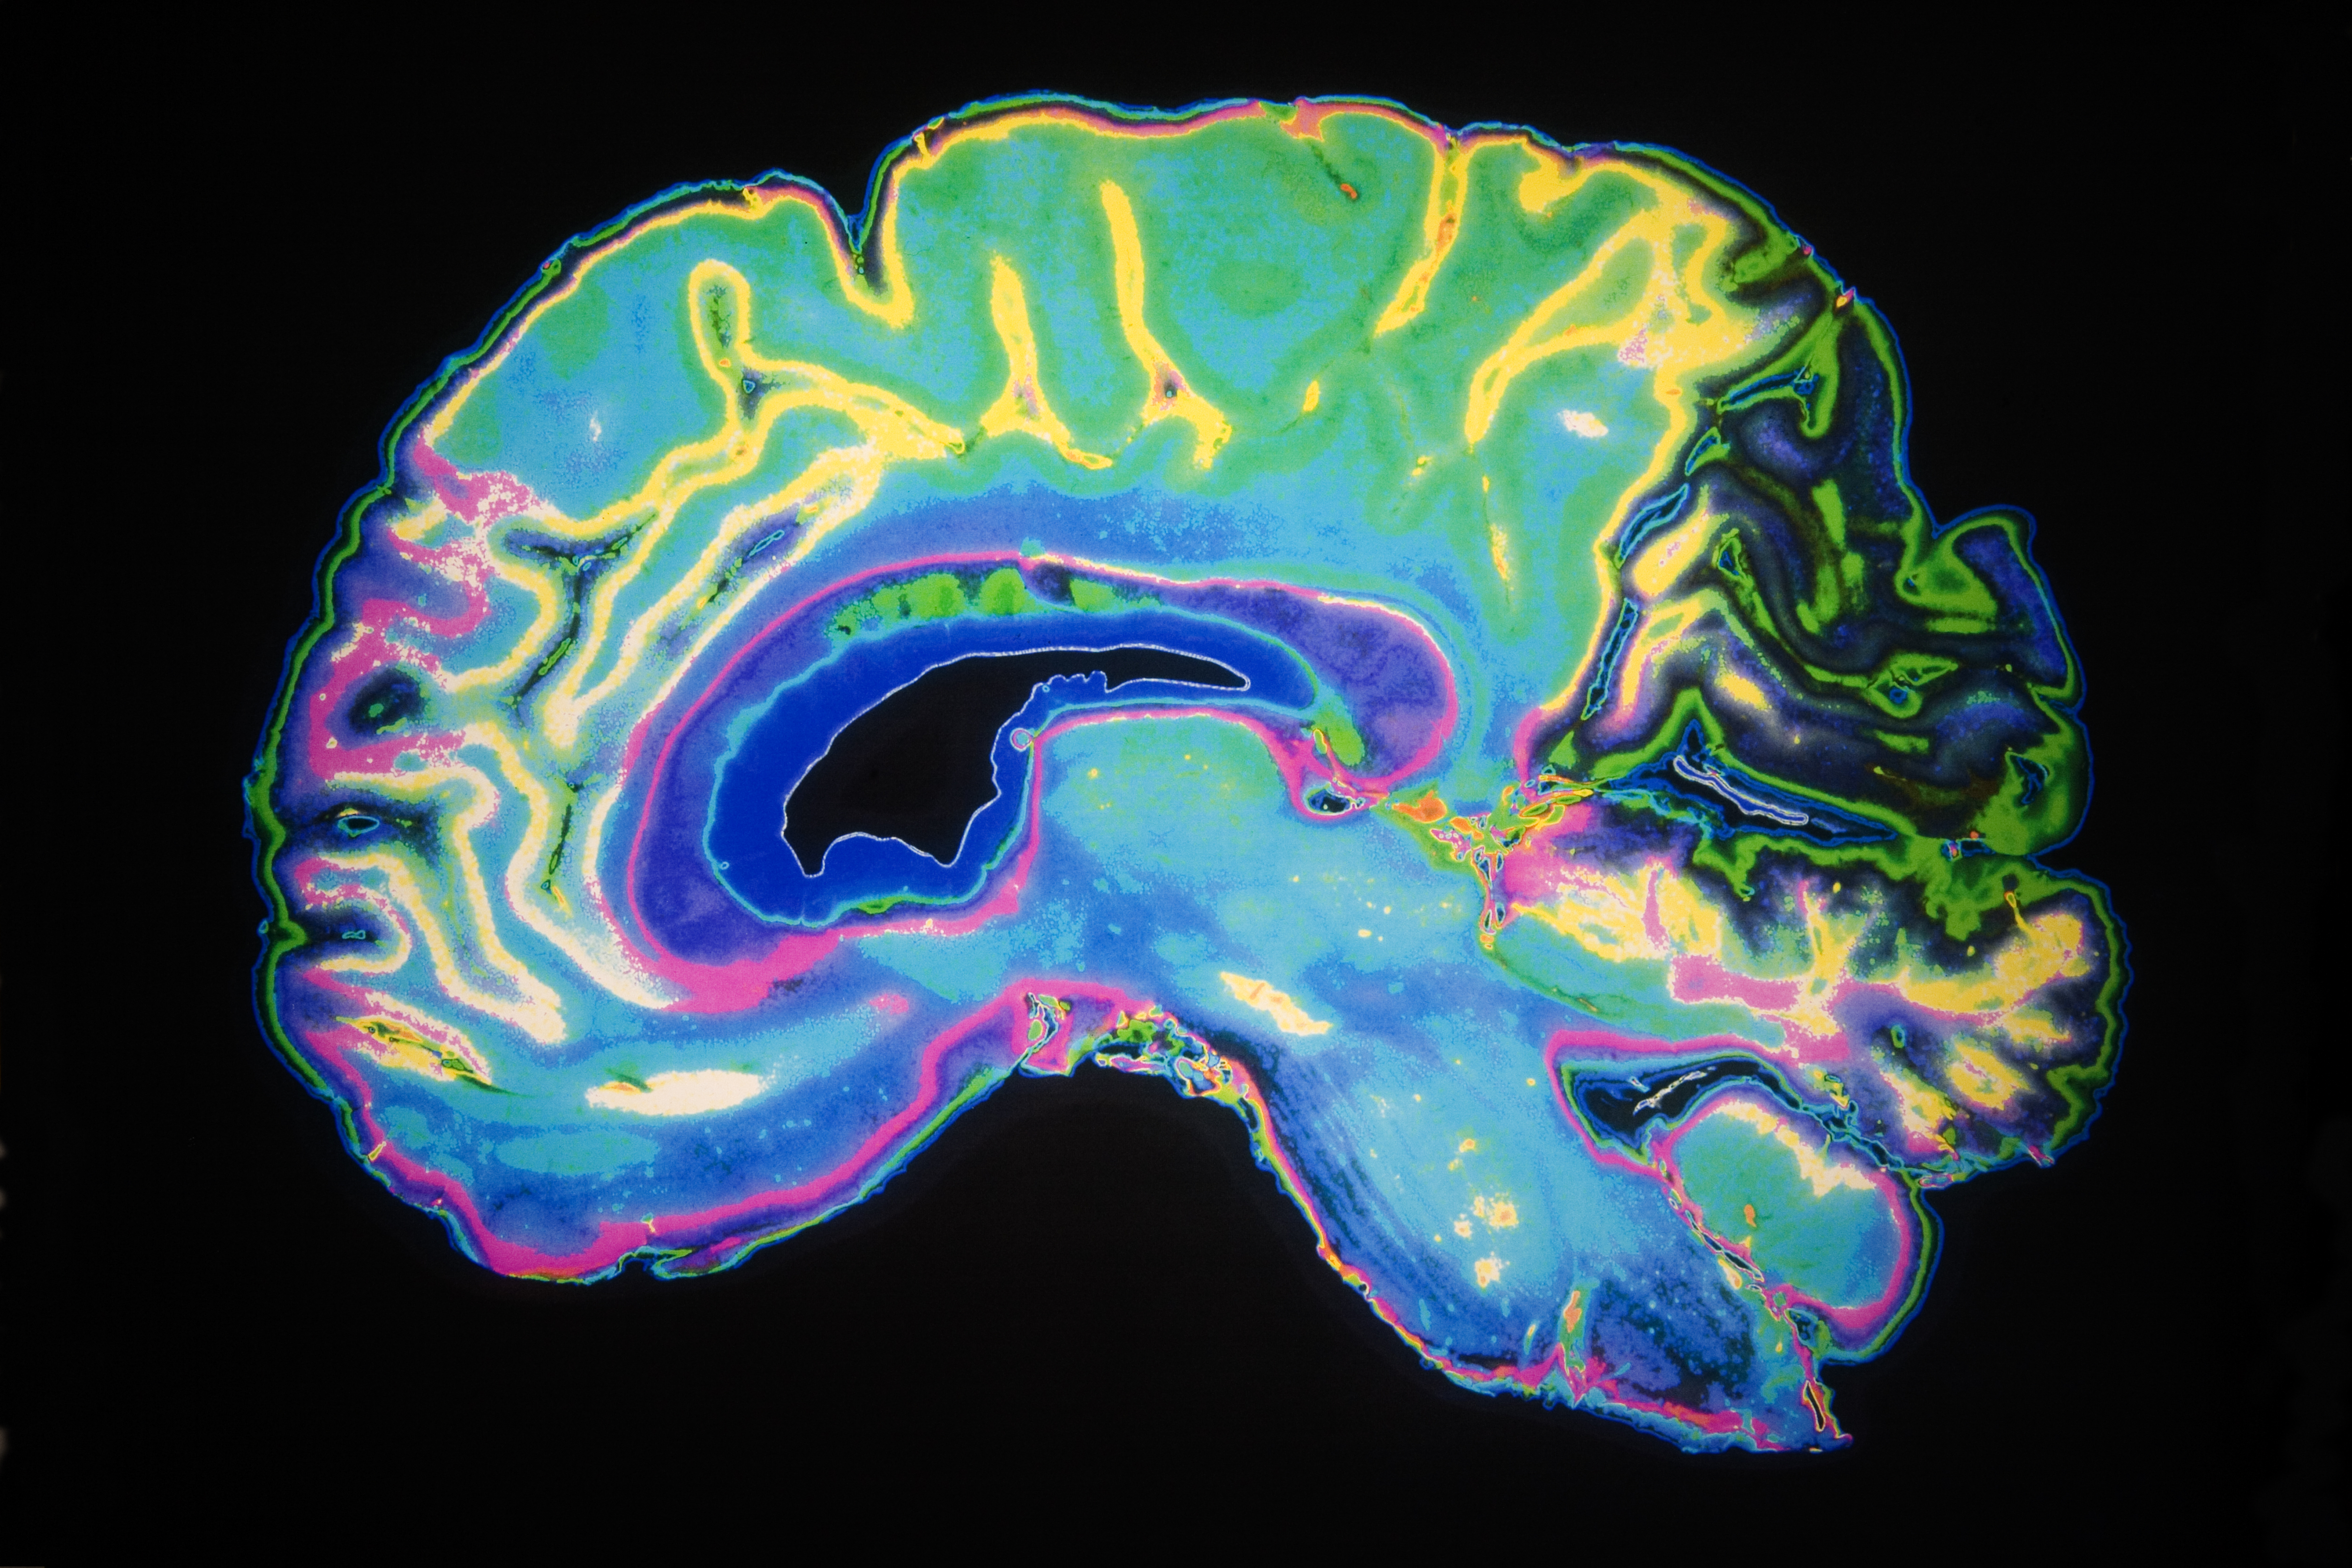

Dementia is a disorder that begins in mid-life – probably in most cases between the ages of 40 and 65 -- but is clinically silent until its end-stage. Tackling it therefore requires an approach to prevention that embraces a wide period of our lives.

Though symptoms are late in onset, dementia is really a disease of mid-life. Brain pathology is present decades before dementia